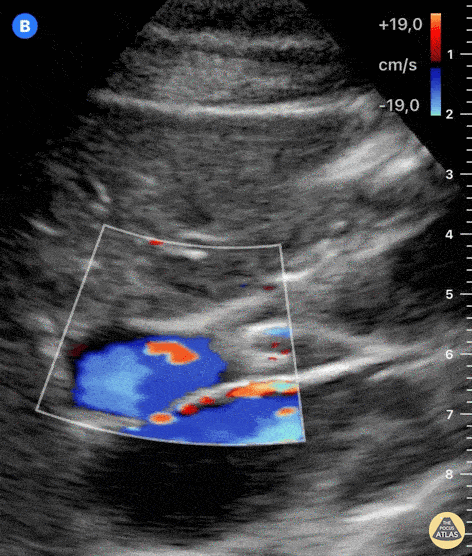

Biliary - Normal Portal Triad - Doppler

Both the adjustment of depth and color-doppler allow for better identification of structures. The large, pulsatile inferior vena cava lies at the bottom of the screen. Color-doppler helps to discern blood vessels from other anatomical structures. Anterior to the IVC and from left to right of the screen, we can see the portal vein and hepatic artery with color-flow. Just above the hepatic artery lies another tubular structure which presents hyperechoic walls and an anechoic lumen; this is the common bile duct. Dr. Felipe Urriola P. Emergency Unit, Puerto Aysen Hospital. Chilean Patagonia.